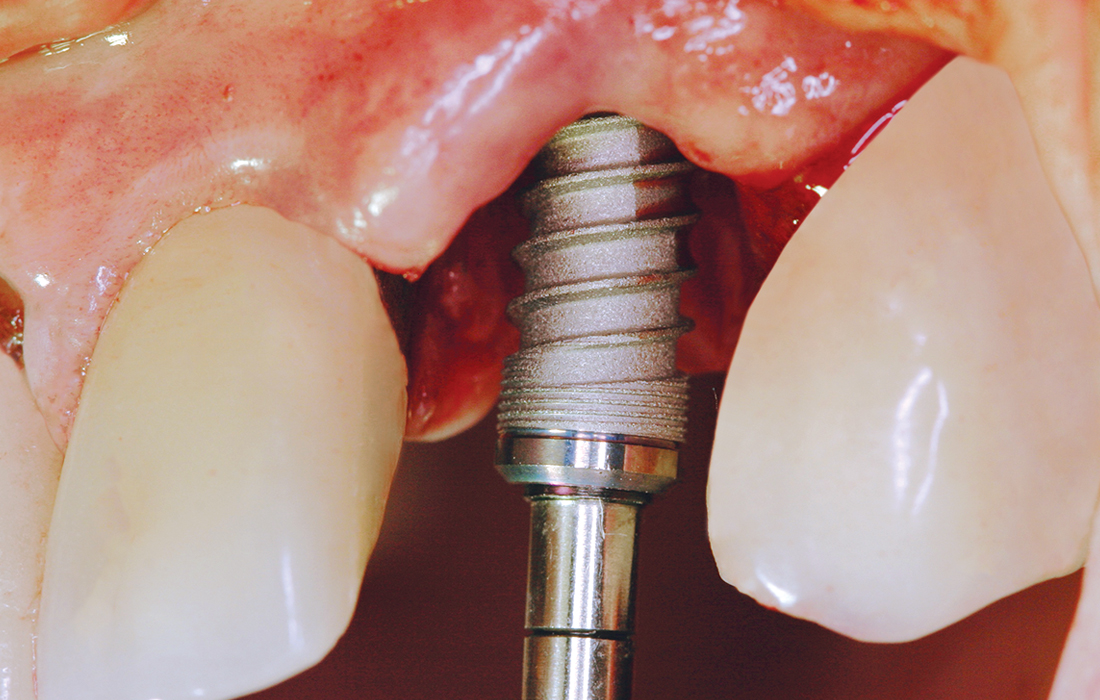

The patient presented with a horizontally fractured tooth #11 and was in a great deal of distress due to the esthetic issues this created. After extracting the tooth, a Hahn Tapered Implant was placed. The pronounced thread design eased placement 1 mm from the facial aspect of the extraction site. High primary stability of 45 Ncm was achieved, allowing for the placement of an immediate provisional crown.